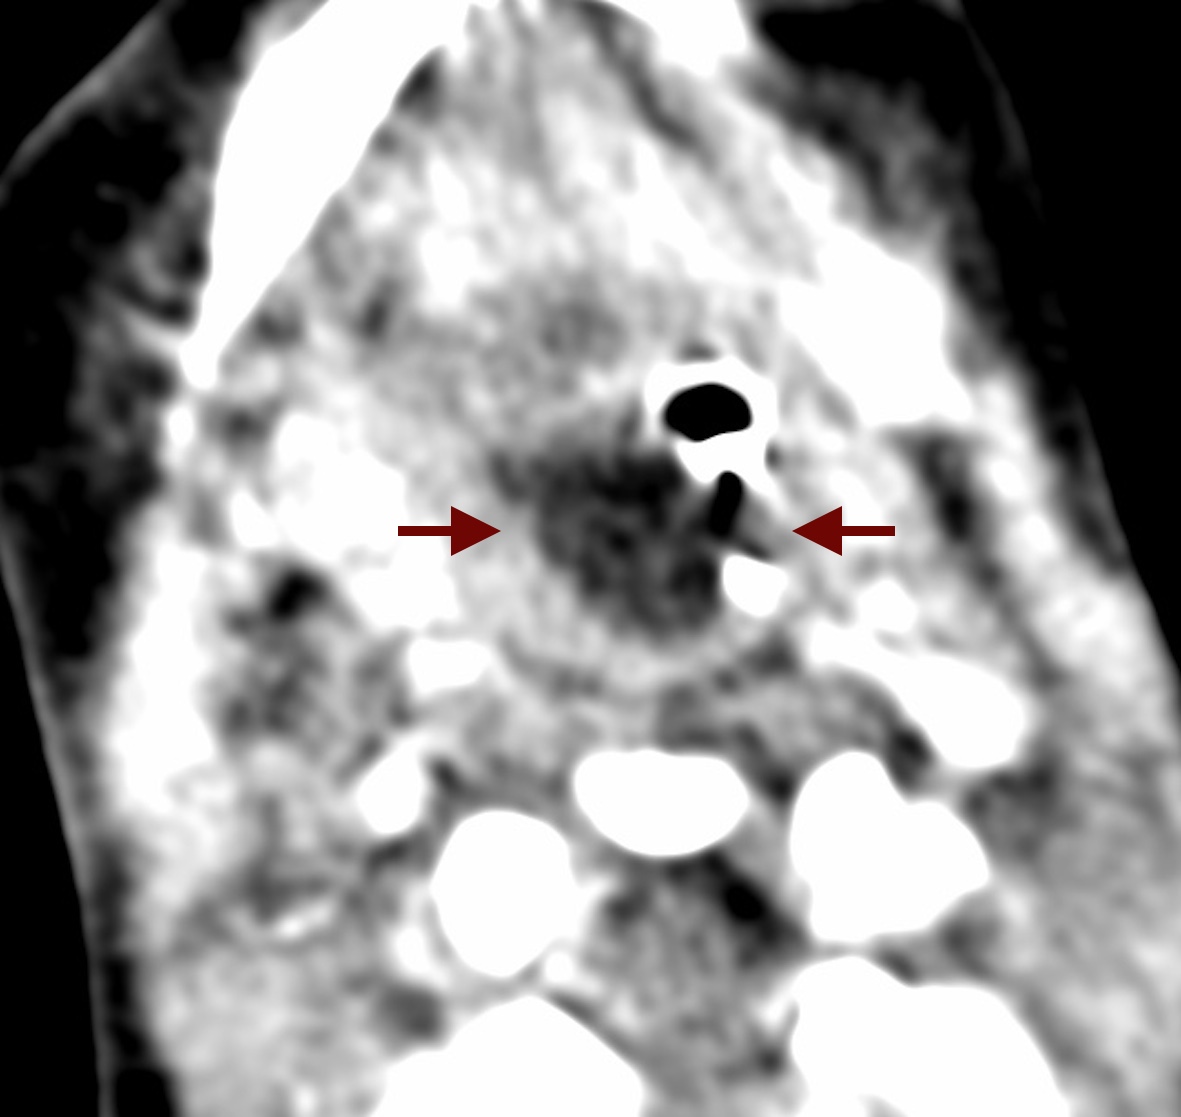

Pharyngeal hairy polyps are rare lesions that arise from the nasopharynx or oropharynx. It occurs predominately in females, with predilection for the left side. Its etiology remains poorly understood. It typically presents in the neonatal period with respiratory distress and feeding difficulties. Imaging is fundamental to identify the high fat content of the lesion. Surgical resection is the treatment of choice. We report a case of a nasopharyngeal hairy polyp causing respiratory distress since birth.